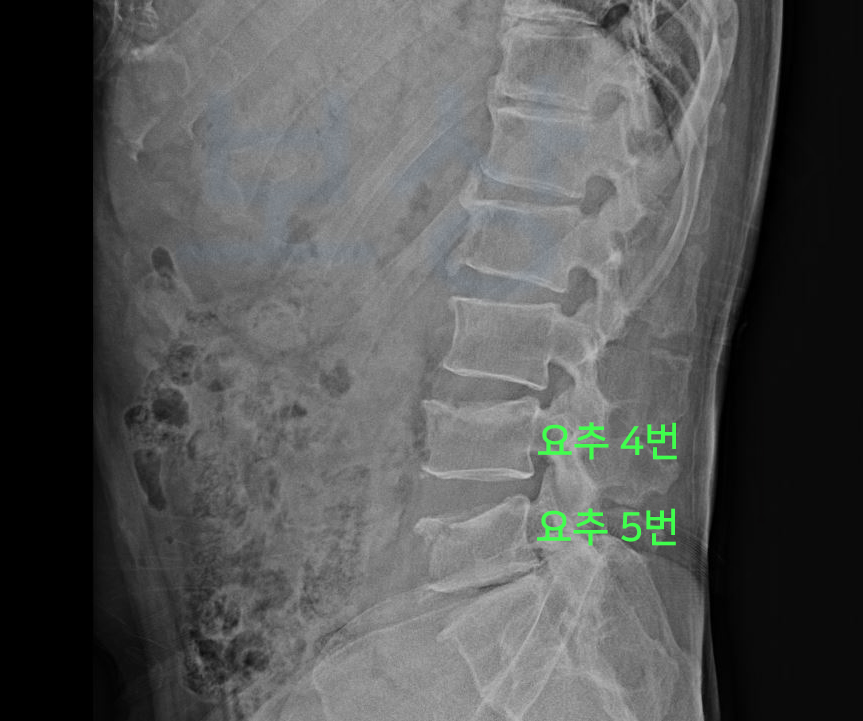

그 결과,

L4 부위의 골절 / L5 부위의 골절

진단을 받으셨습니다. L 은 Lumbar의 약자로서 4번, 5번은 척추체의 숫자를 의미합니다.

image

위 사진을 보시는 것처럼 요추 4번 5번이 압박골절되어 척추체의 전면이 주저앉은 모습 보이시죠? 요추 4번 5번 압박골절로 곽@@님은 TLSO 보조기를 착용하며 최소 12주간 입원 및 요양을 하셔야 했죠.